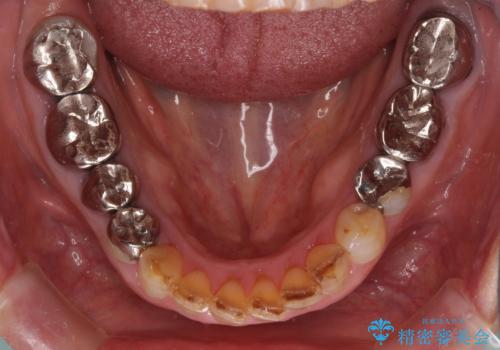

- 奥歯に装着されている銀歯を全て外したいとのことで来院された患者様です。

土台に含まれている金属も含め、奥歯の金属は全て除去し、オールセラミッククラウンやセラミックインレーにて治療することとしました。